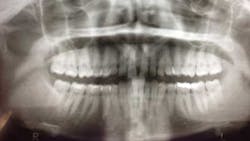

When a full permanent dentition is present (with the exception of impacted canines), the labial/palatal position of the canine will have an influence on what the provider can do. (1) Arguably, obtaining a CBCT is considered mandatory and will allow for a more inclusive treatment plan creation. If angulation is favorable, then consideration to remove the primary canine and wait six months to see if there is movement of the permanent canine is an option. If extraction of the canine(s) is needed, then a premolar substitution, which is dependent on occlusion, can be used in the space. An implant can also be an appropriate alternative. When pulling a canine into the occlusal arch, there is risk involved. Trauma to adjacent teeth (root resorption) and ankylosis are some of the most common complications.The patient was put in full orthodontics and referred to a surgeon for extraction of the primary canines, exposure, and placement of retention on the impacted canines to pull them directly down from their current position.

A ballista appliance was used to prevent a facial pull of the canines in order to avoid and prevent resorption of the roots of the lateral incisors. As movement progressed over the course of the next year, eruption of the canines was considered a success. Once in position, they will be pulled facially into occlusion.

The patient is pleased with the progress reached thus far and is ecstatic at the anticipation of a successful outcome.